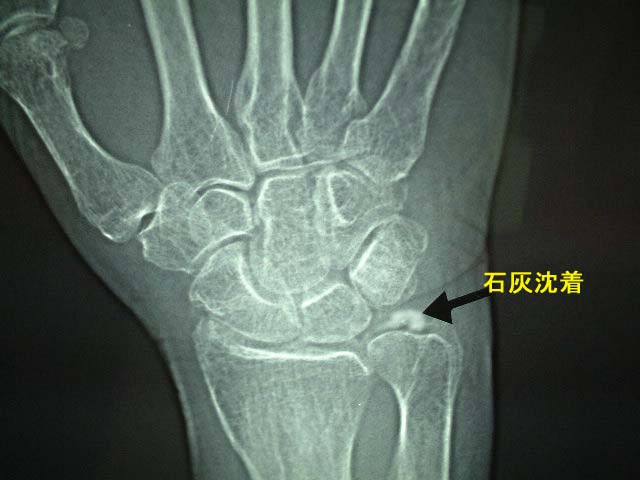

手部石灰沈着

手部の腱や靭帯、関節包の周囲に石灰物が沈着する疾患です。原因は不明です。中高齢者に多く認められ、症状として手関節や手指に激痛、脹れ、発赤(赤くなる状態)を認めます。

レントゲン検査で

手関節部手指に石灰物が確認できれば確定診断されます。稀に若年者にも発生することがありますので要注意です。なお痛風や偽痛風の鑑別が必要です。